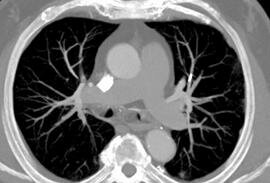

A Rare Cause of Acute Dyspnea in the Emergency Department: Pulmonary Cement Embolism

J Wermuth, MD, S Meckel, MD , FT Wetzel, MD, R Bingisser, MD